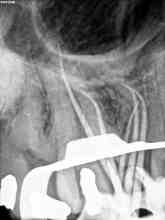

( Otra molar superior con 3 conductos mesiales)

Esta última foto corresponde con un caso de un primer molar superior que la Rx no me esperaba que tuvieses tres conductos mesiales:

Son casos complicados, este en particular, por la ligera curva apical, que se agrava con la curva coronal, con lo que debemos  aliviar modificando la apertura y acceso del tercio coronal con ultrasonidos e instrumentación.

Usamos los sistemas Pathfiles y las Mtwo, consiguiendo una buena preparación  de los conductos